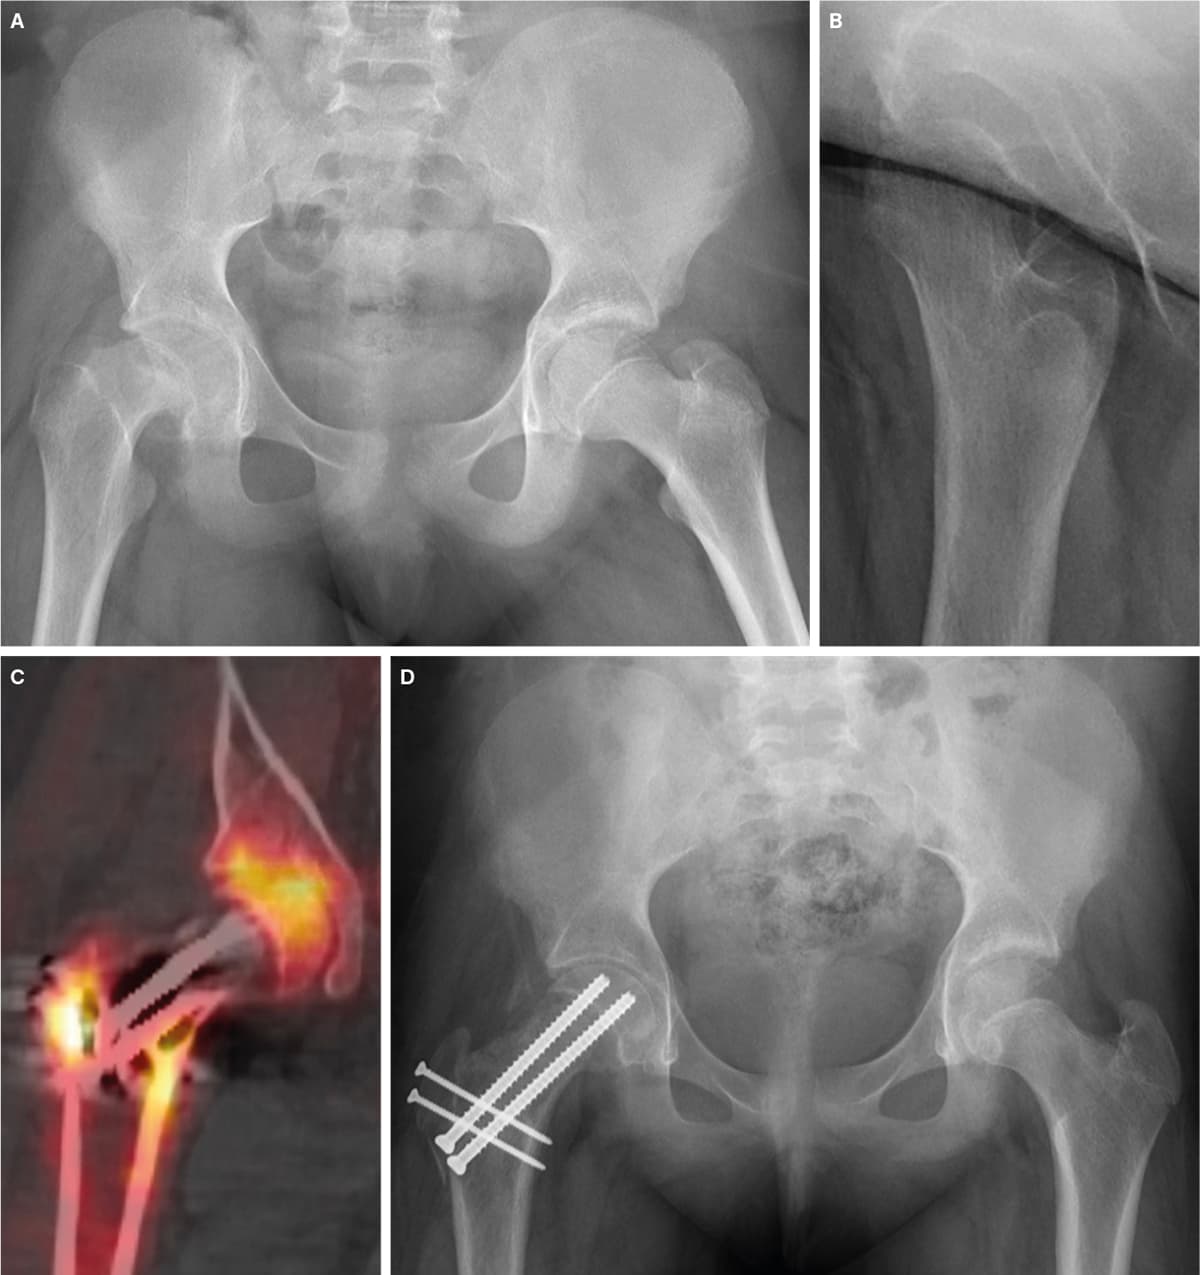

En 13-årig pige kom på skadestuen med stærke smerter i højre hofte og lår. Hun var faldet, havde slået højre hofte og kunne ikke støtte på benet. Der havde været smerter i højre lår i de foregående fire måneder. Røntgen af bækkenet anterior-posteriort og sideoptagelse viste en ustabil hofteepifysiolyse (SCFE) på højre side (A + B). På en børneortopædisk afdeling blev der foretaget åben reposition ved hjælp af hoftedislokationsteknik [1-3]. Ved denne højtspecialiserede operation monitoreredes blodforsyningen af caput femoris ved intraossøs trykmåling. Ved postoperativ knogle-SPECT/CT bekræftedes vitaliteten (C). Vægtbelastning og genoptræning påbegyndtes efter seks uger (D).

SCFE er en sjælden sygdom, som primært rammer 9-15-årige. Da mange børn får smerter fra knæ og lår, kan diagnosen være vanskelig at stille [4]. Klinisk vil der ofte være halten, nedsat indadrotation i hofteleddet og evt. benlængdeforskel. Asymmetri ved undersøgelse af underekstremiteterne bør altid føre til yderligere udredning [5]. Ved mistanke om SCFE må barnet ikke vægtbelaste på benet, før billeddiagnostisk udredning med røntgenoptagelse af bækkenet i to projektioner er foretaget (ideelt anterior-posteriort og Lauensteins projektion).